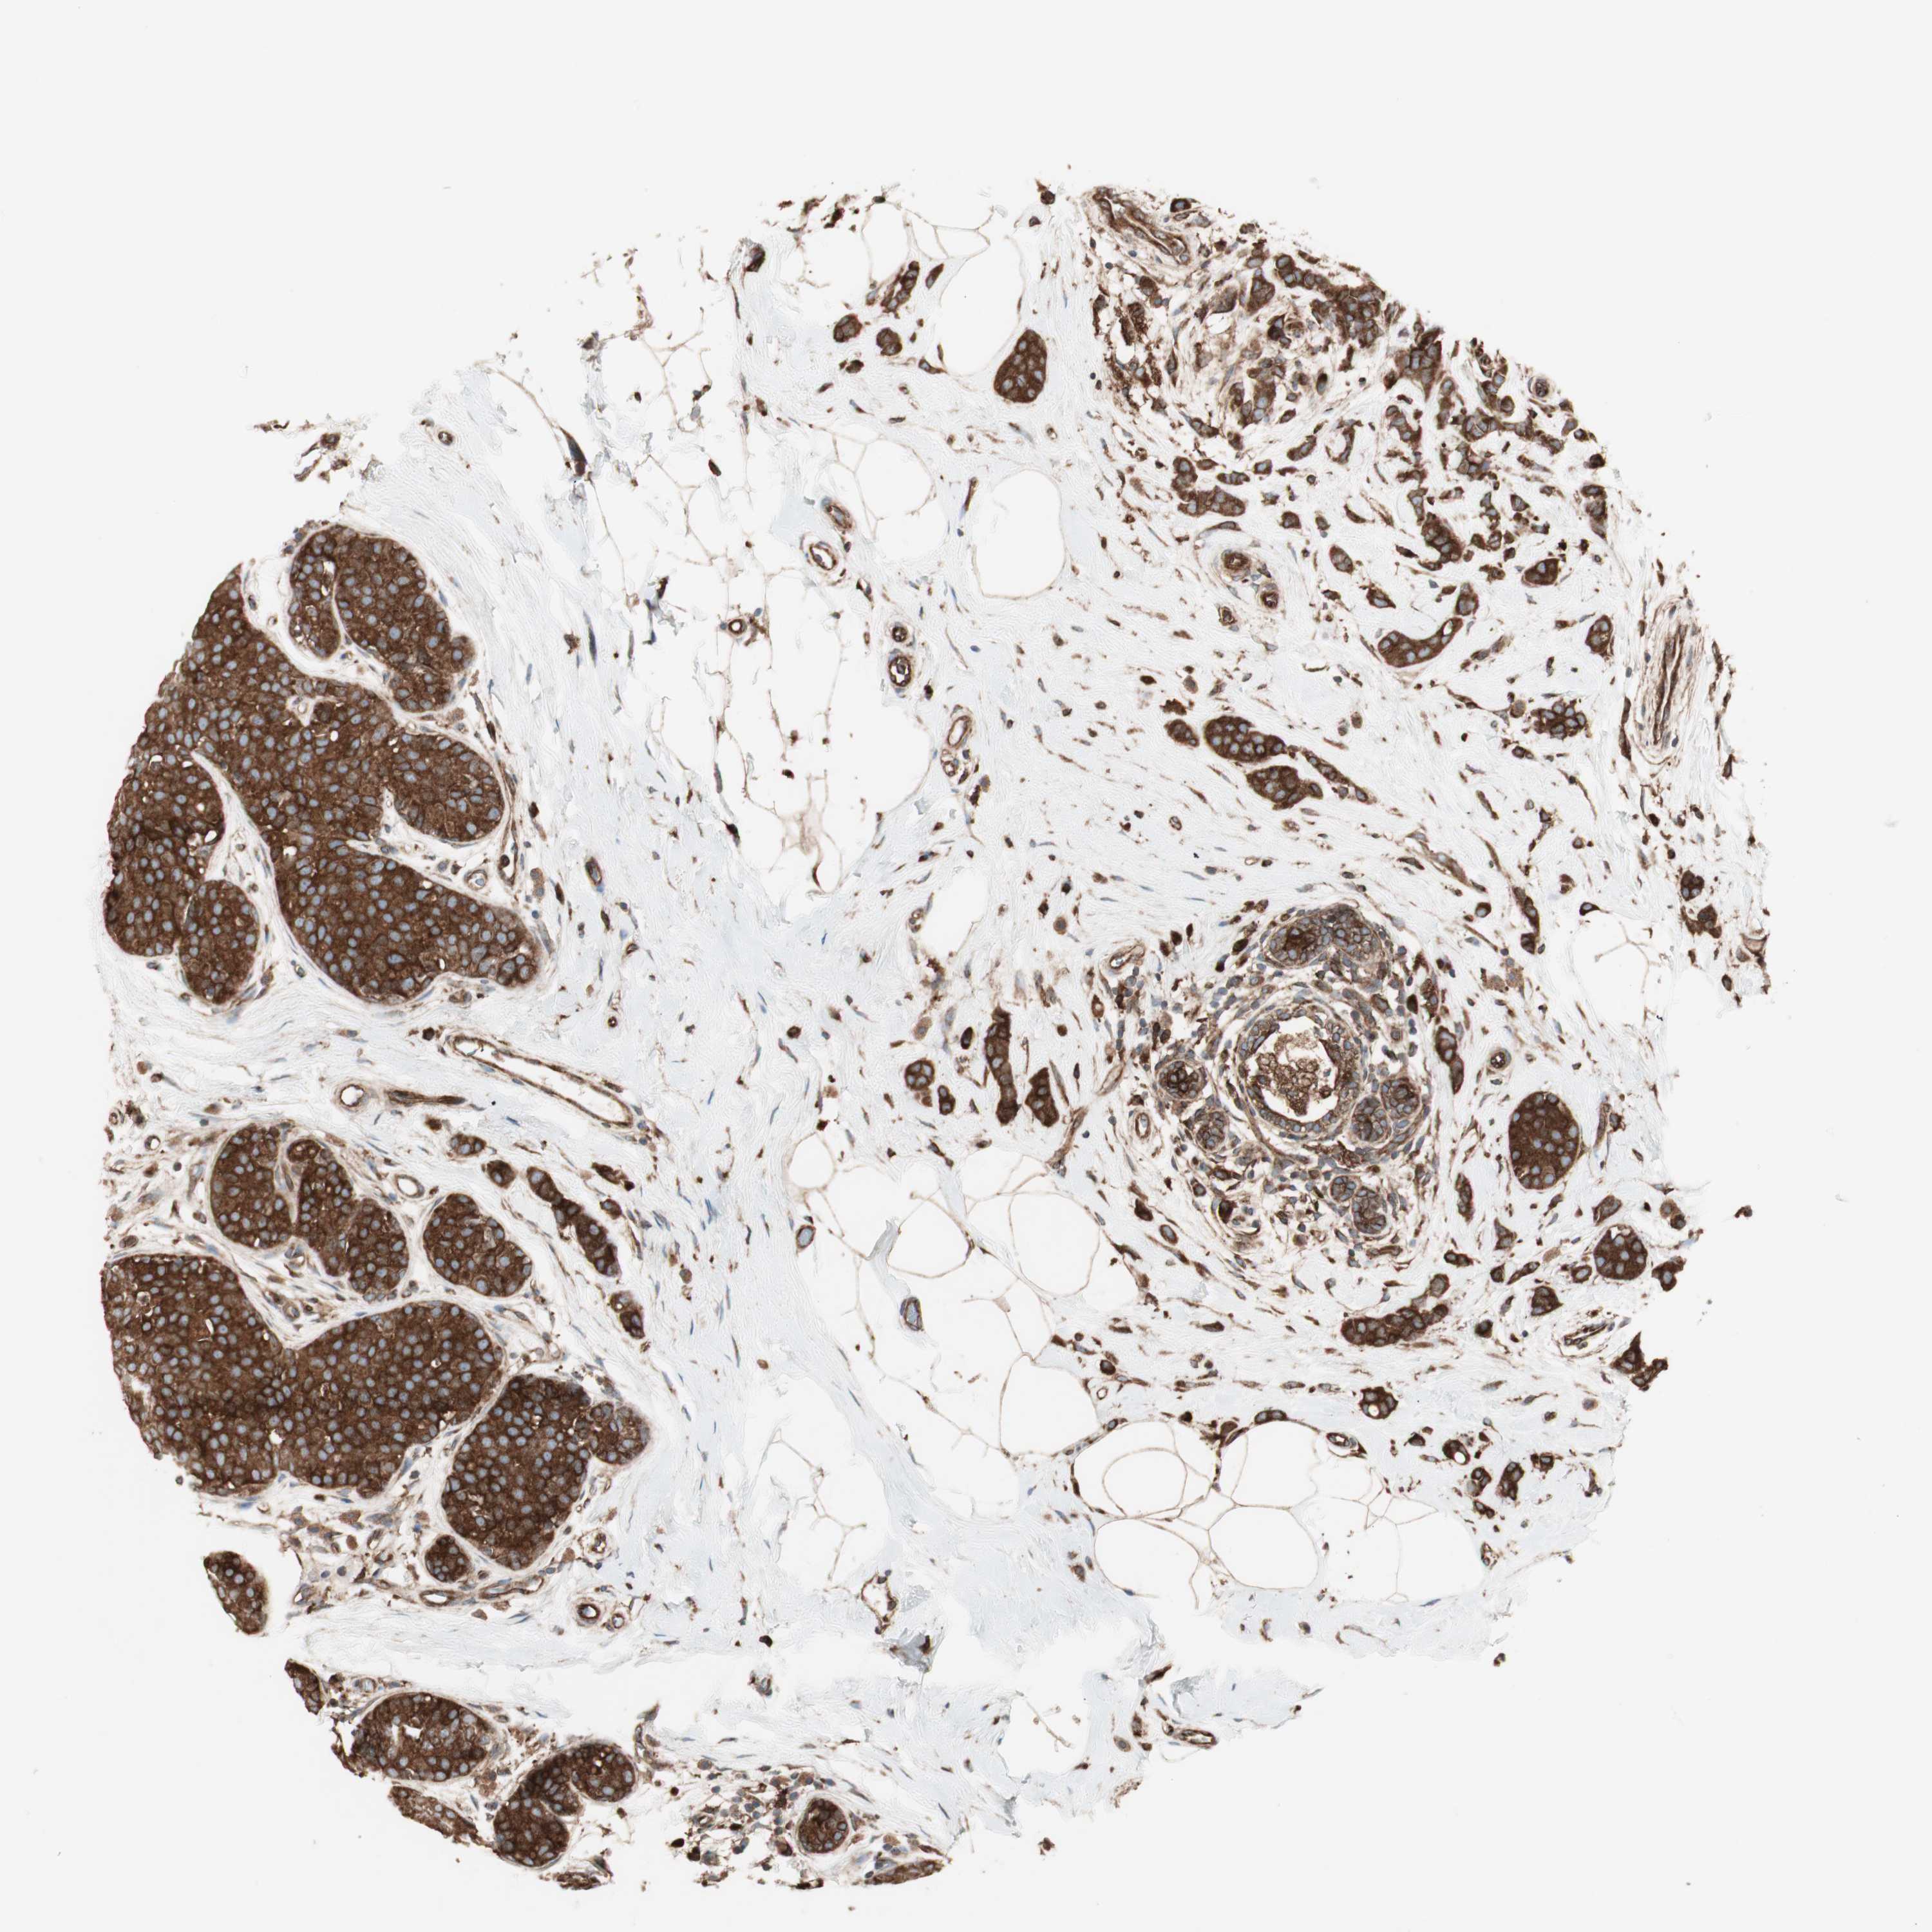

CANCER BREAST CANCER Show tissue menu

BRCA TCGA BRCA VALIDATION PROTEIN EXPRESSION

ANTIBODIES

AND

VALIDATION

RAB5A is not prognostic in Breast Invasive Carcinoma (TCGA)